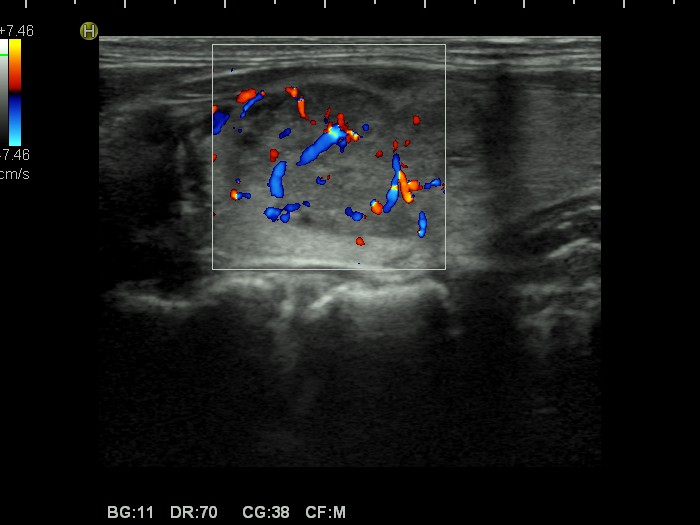

Left lobe, transverse view, color Doppler mode. The nodule has intranodular blood flow.